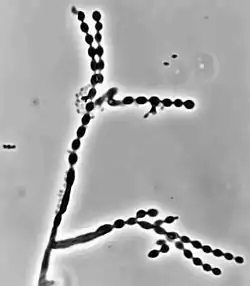

Cladophialophora carrionii is part of a group of melanized fungi, also known as "black yeasts" because its mycelial form has a dark green colour and its conidia have brown pigment.[2][6] Colonies grow at a modest rate on Sabouraud dextrose agar.[1] The conidia of C. carrionii are unicellular oval-shaped spores that are distinguishable due to the presence of two lightly pigmented scars.[6][7] Conidia vary in length (1.5-3.0 × 2.0-7.5 μm).[1] Its long conidiophores are similar to the genus Cladosporium, which comes from the Latin word "clado", meaning branched.[1] The genus Cladophialophora is distinguished from Cladosporium because in addition to chains of conidia, members of the genus Cladophialophora also produce phialides.[8] Cladophialophora carrionii is a dimorphic pathogen that changes states from a mycelial form to a muriform, yeast-like state once it invades its host.[3] Muriform cells are golden-brown in colour due to melanin deposition and have thick cell walls.[2][3]

Like many other black yeasts, C. carrionii is sensitive to temperatures above 37 °C.[6] It can be distinguished in culture by the presence of its urease enzyme hydrolyzing urea[9] and its inability to liquefy gelatin.[7][10] Altering temperatures or micronutrient levels such as calcium and phosphate affects whether C. carrionii is in the mycelial or muriform state.[2] The fungus transforms to muriform cells under conditions of temperature between 25 °C to 37 °C, 0.1 mM Ca2+, and a pH of 2.5.[8] It produces multiple conidia in long, straight chains that bud off the hyphae, with the youngest conidia farthest from the hyphae.[2] There is no sexual state known for C. carrionii.[6]